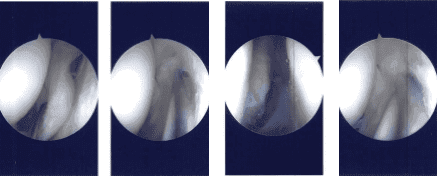

There was a small patch of grade 2 to grade 3 arthritis on the medial patellar area, which was cleaned. Examination of intercondylar notch was intact ACL. Examination of the tibiofemoral joint medial marginal meniscus, which was cleaned using shaver and upbiters. There was no tear in the medial meniscus.

There was a large popliteal hiatus with the possible tear going into the posterior horn of the lateral meniscus, which was incomplete. A thorough examination was done, and the debridement was done. The decision was made not to repair it at present because it seemed to be an extensional popliteal hiatus.

Intraoperative Arthroscopy Images